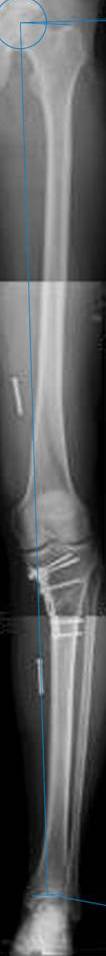

картинки оперированного пациента 40 лет, травма в 2006 году.

оперирован 06.11.2009г - корригирующая остеотомия большеберцовой кости.

Я картинку собрал с некоторыми погрешностями, если провести отвес от центра вращения головки бедра до середины голени (на пациенте),то имеется небольшой вальгус (гиперкоррекция)конечно она (гиперкоррекция) не достигает 10 гр, но 5 гр она достигает.

К сожалению, не очень удачный пример. Если верить Р-граммам, имеет место быть дисплазия мыщелков бедренной кости с наклоном суставной линии. Это уже создает сложности получения хороших отдаленных результатов. Кроме того, по классике, необходима гиперкоррекция с созданием вальгуса 7-10 градусов для максимальной разгрузки медиального отдела КС. Если верить укладке, то линия сустава имеет четкий варусный наклон, поэтому результат операции м.б. кратковременным. В этих случаях показана двойная остеотомия бедра и тибии.

Alexander Artemiev 10 Ноябрь 2009, 15:54

Впечатление искажает неправильная укладка.

Если сделать правильно, то видно, что бедренная кость в порядке, а цель остеотомии (низкой, кстати), не достигнута вовсе.

Сохраняется варус. Для того, чтобы создать вальгусную гиперкоррекцию, не моделируя при этом откровенный Х голени, можно сделать медиализирующую остеотомию.